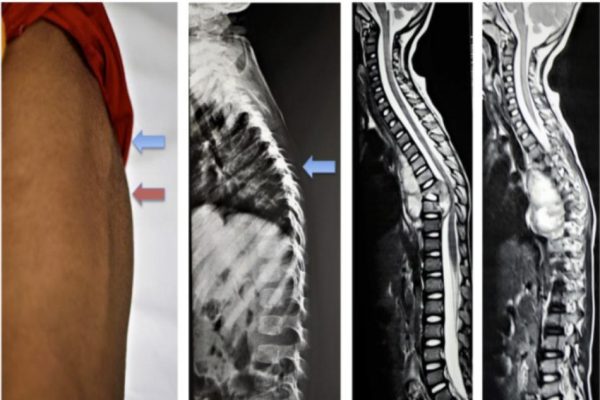

Ứng dụng các kỹ thuật mới trong chỉnh vẹo cột sống